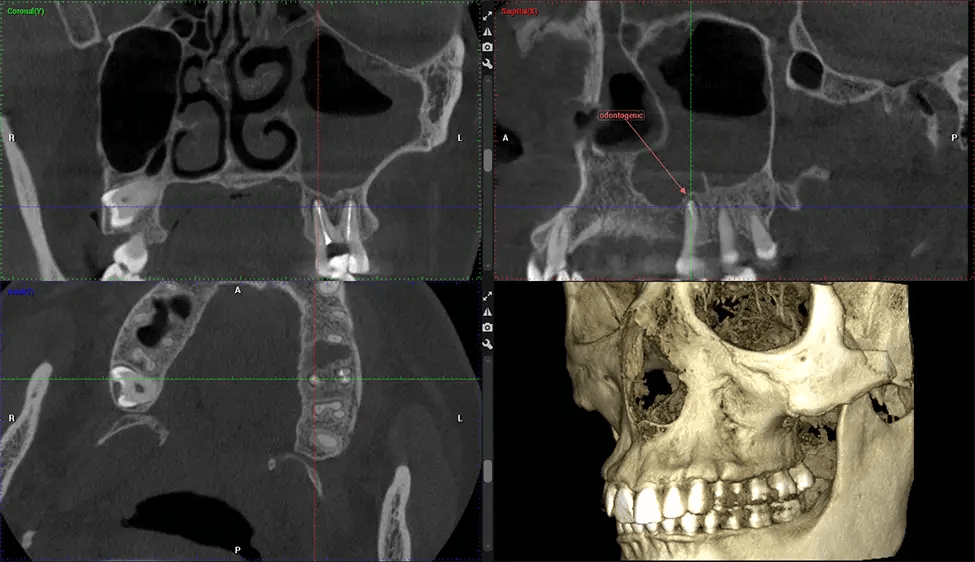

This 3D scan, called cone beam computed tomography, gives your dentist a more complete image of your oral anatomy and disease processes than a traditional X-ray. Unlike conventional X-rays, which capture a 2D image of your mouth from various angles, a 3D scan takes multiple digital X-rays for one image. It provides a complete view of your jaw, teeth, nerves, and soft tissues. This enhanced view allows dentists to detect minor issues not visible in traditional 2D scans, such as impacted wisdom teeth or bone fractures in the sinus cavity.

There are many benefits to using CBCT technology, especially compared to the traditional 2D X-ray format. One of the most significant advantages of CBCT scans is that they provide much more information than traditional X-rays. A scan lets your dentist see images from all angles of your jaw and mouth, including your sinuses, nasal cavity, cheekbones, and other surrounding areas. This added information helps your dentist craft a comprehensive treatment plan that addresses all aspects of your oral health.

Another significant benefit is that 3D imaging provides more precise images of your bone structure. These images are more detailed, providing you with a more accurate diagnosis. An accurate diagnosis means better treatment for you.